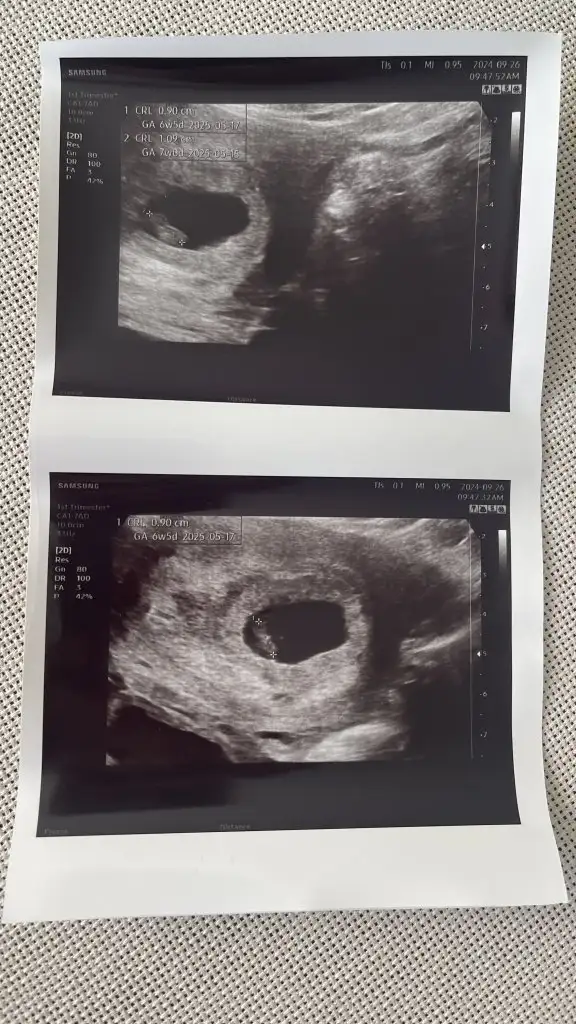

Bnm şuan 11+3 haftalık gebeyim üç kızım var hepsi sol taraftaydı bu hep sağda ve geçen doktor a gittim çıkıntı var erkeğe benziyor dedi net bir şey söylemedi bunda çok mide kazıntım var yemek ler den nefret ediyorum artık jiç görmek bile istemiyorum bu çok farklı ama içimde bir umut inşallah oğlum olucak doktor erkeğe benziyor dedi çıkıntı var dedi kızlarda hiçbir doktor böyle söylemedi inşallah sağlıklı bir oğlum olur ama kız solda erkek sağda ve kızlar da karın daha yukarıda ve geniş yuvarlak olur erkek şerde daha sivri aşşağı da olur bnm karnım çok erken çıktı neden bilmiyorum bana dua edin Allah ım erkek evlat sevgisi ni tattırsın inşallah